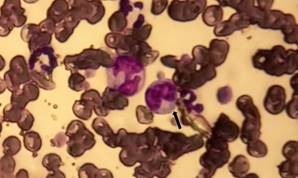

En la revisión de los frotis teñidos se encontraron las mórulas características de la infección por Ehrlichia spp.Figuras 1 y 2.

Figura 2 Frotis sanguíneo 800x, en él se observa glóbulos blancos con mórulas dentro del citoplasma (flecha).